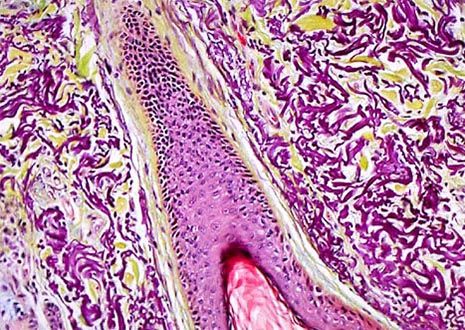

Skin Hair Follicle

Hair does not exist and grow alone, but is part of the pilosebaceous system, which also includes follicles, papillae, and sebaceous glands. A typical human has approximately 100,000 hairs on his or her scalp and loses about 50 to 100 strands a day.